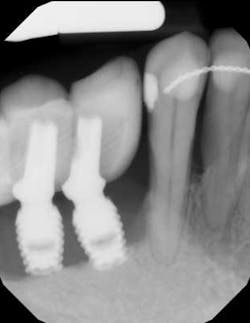

Recently, a regenerative surgical protocol that uses both mechanical and chemical means for implant surface detoxification—together with a bone graft and/or substitute including coverage with a barrier membrane and a two- to 10-year follow-up period—has been shown to have a 98.8% implant survival rate. The results of this study were based on peri-implantitis treatment of 170 consecutive dental implants in 100 patients. (13) In that specific study, an air powder abrasive was utilized as part of the surface decontamination.